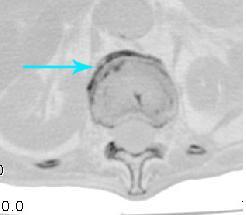

男:89岁因外伤后2天行ct检查。请各位战友讨论图中所指是否是骨折和形成该影像的原因(扫描层面位于椎体中份)。

老年性骨质疏松,椎体前缘出现双边征支持压缩骨折。椎体骨质稀疏,似有破坏,警惕溶骨性骨转移。

椎体前缘双边征,其后椎体内密度增高均提示压缩性骨折

椎体前缘呈双边征 考虑 压缩性骨折,椎体退行性病变。

我的报告1:腰椎骨质退行性改变。

2:t12改变考虑压缩骨折?请结合临床。